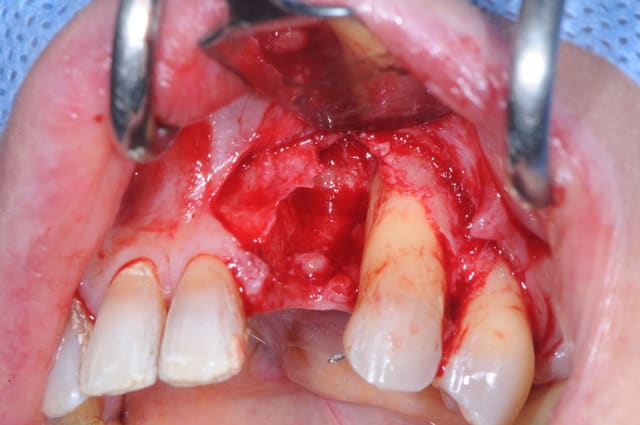

maintenant, la phase reconstruction de la zone antérieure.

1 défaut osseux (y a plus grand chose!)

2 essayage de la membrane titane

3 stabilisation de la membrane

4 comblement osseux

reste plus qu'à attendre...